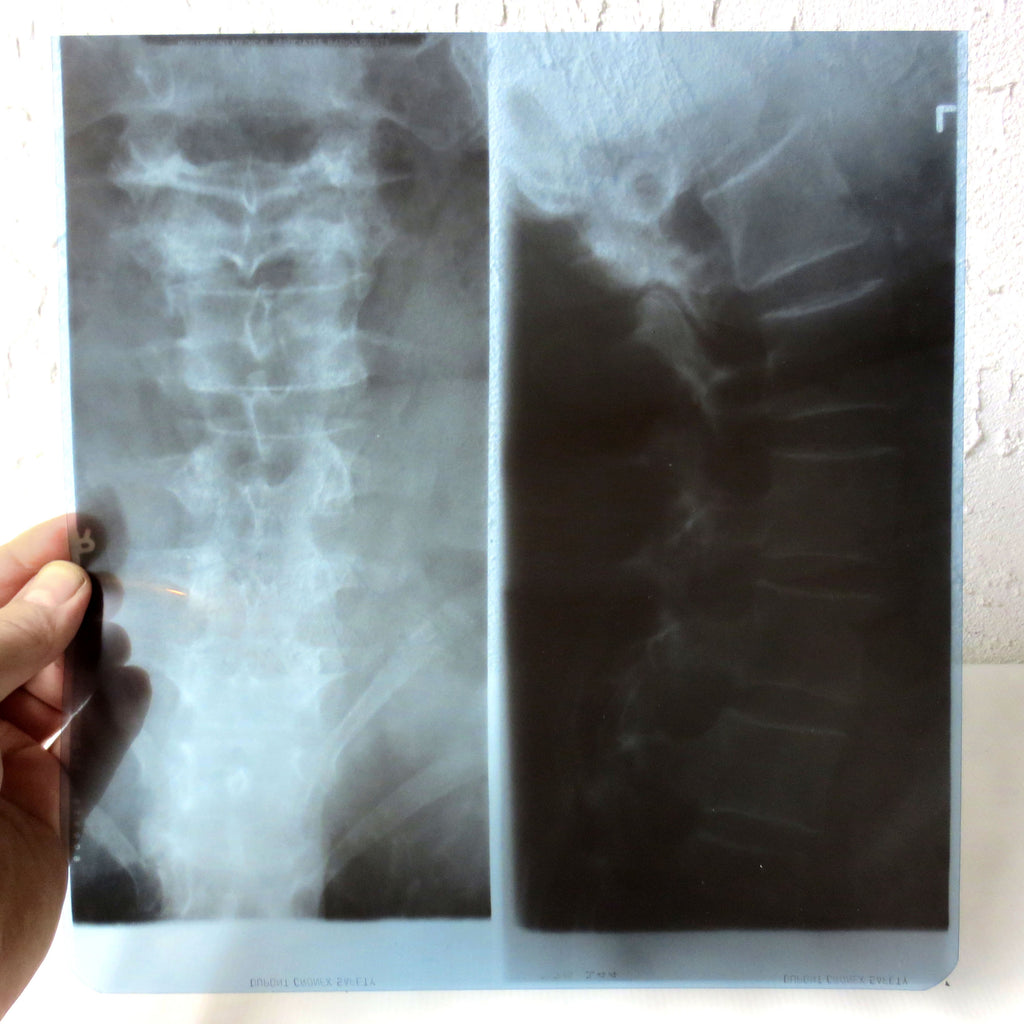

Excellent condition, no tears, flat and thick blue plastic sheet. Actual X-ray of a patient's Cervical Vertebrae (neck), marked Dupont Chronex. Can easily be framed with a light on back to see details clearly. Great addition to your medical collection or as a prop. Will be shipped flat in a rigid and waterproof package. Measures 10 X 11 inches.